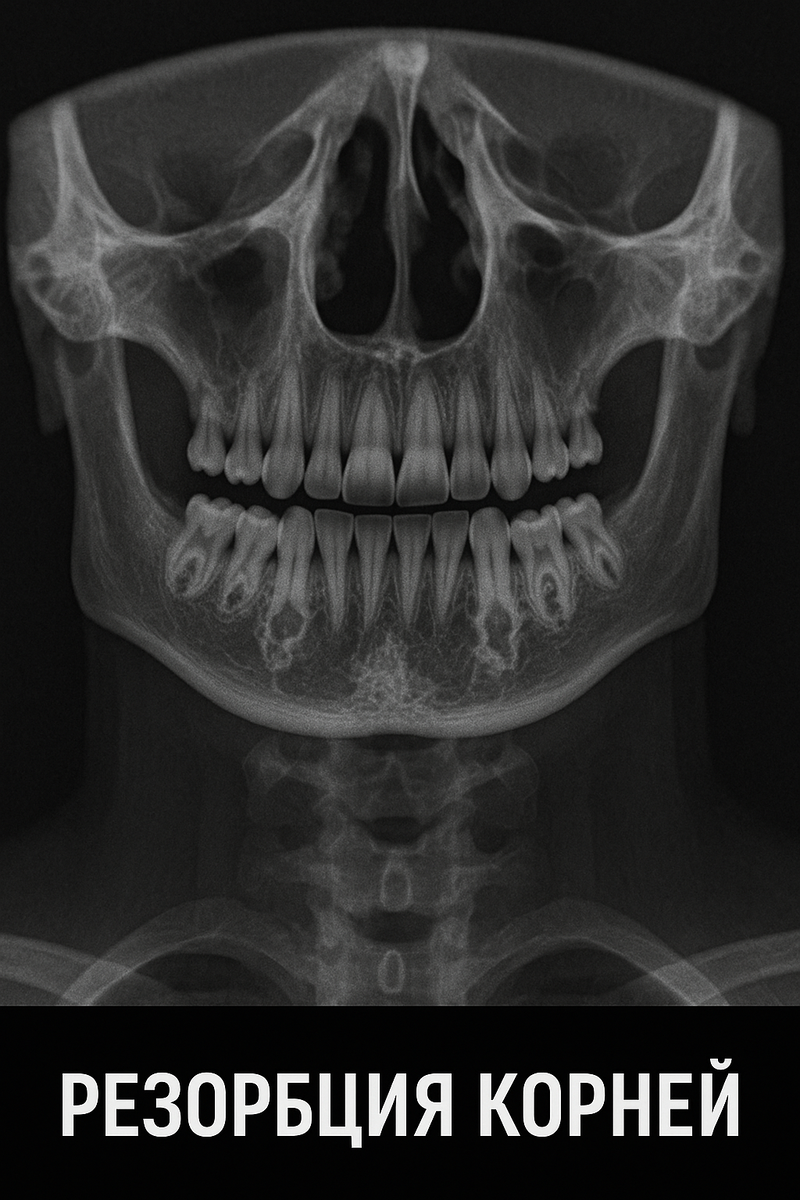

✔️ Неправильное давление вызывает резорбцию корней (рассасывание)

Неправильное давление вызывает резорбцию корней (рассасывание)

• У подростка разрушились корни передних зубов